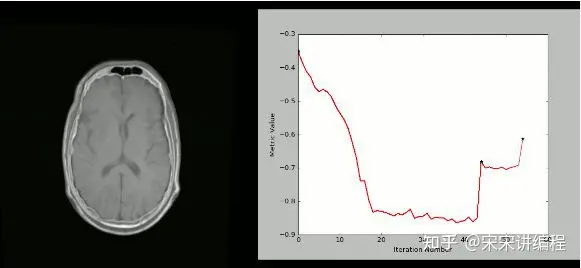

8.SimpleITK

ITK(Insight Segmentation and Registration Toolkit)是一个“开源,跨平台系统,为开发人员提供了一套用于图像分析的广泛软件工具。

SimpleITK是一个基于ITK构建的简化层,旨在促进其在快速原型设计,交易以及解释语言方面的应用。”它也是一个图像分析工具包,具有大量组件,支持一般过滤操作,图像分割和配准。SimpleITK是用C ++编写的,但它可用包括Python在内的大量编程语言进行操作。

资源

有大量的Jupyter Notebook说明了SimpleITK在教育和研究活动中的应用。

Notebooks使用Python和R编程语言演示如何使用SimpleITK进行交互式图像分析。

用法

使用SimpleITK和Python创建可视化的严格CT / MR配准过程: